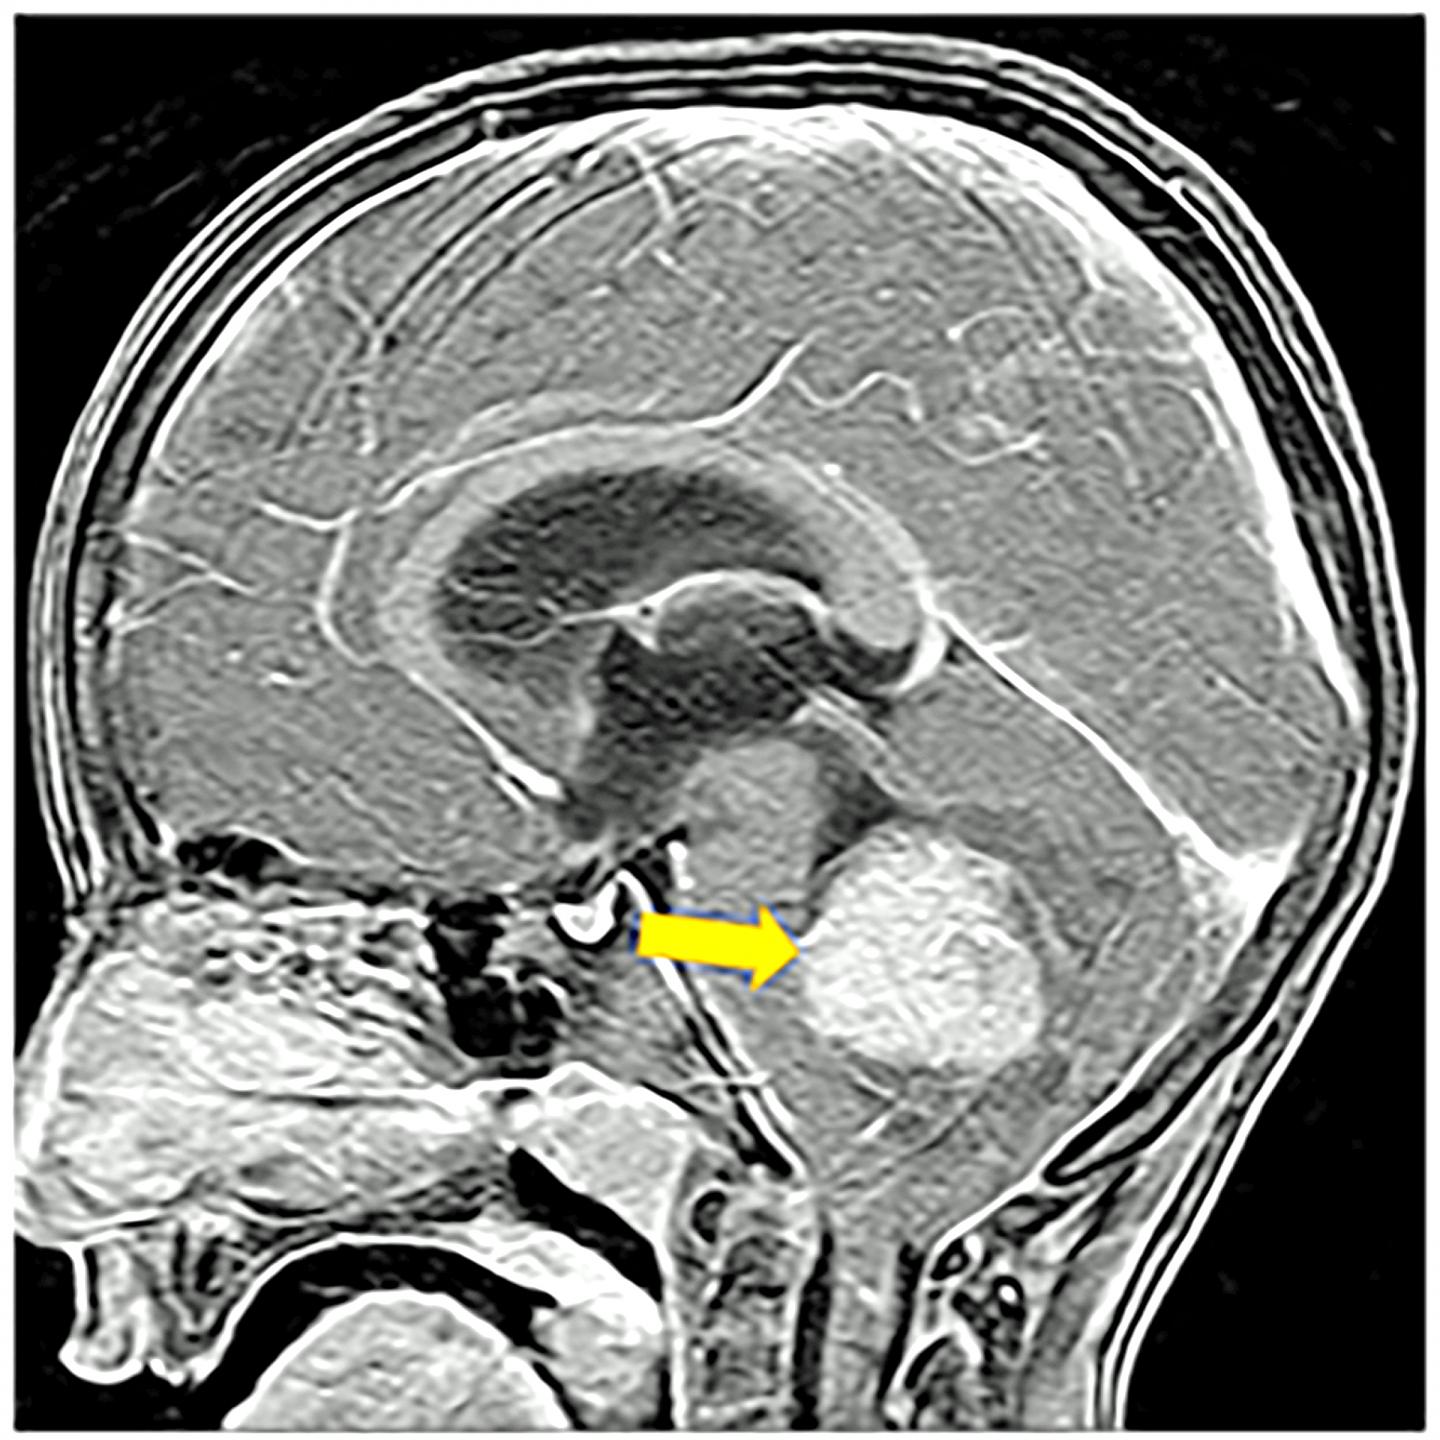

image: Scientists looking for effective treatments against an aggressive form of medulloblastoma brain cancer, like the tumor shown in this MRI image of a child, report using a powerful new computer-assisted technology called single-cell transcriptomics to discover genetic drivers of the disease. When they blocked those molecular pathways it stopped the cancer in laboratory models of the disease. Researchers report in the journal Cancer Cell that there are existing drugs already in use for other forms of the disease that could be used to treat the aggressive cancer.

CINCINNATI - One of the most common brain cancers in children, Sonic Hedgehog (SHH) medulloblastoma, also is one of the more survivable for most kids. Unfortunately, for a subset of patients the cancer resists treatment and relapses with a vengeance to then turn deadly.

One treatment target proposed by the study is the HIPPO-YAP/TAZ molecular pathway, which can be targeted with an FDA-approved drug already in use for cancer treatment. The pathway is normally responsible for helping control programs that turn cell growth on and off to ensure the body's tissues and organs are accurately shaped and sized. In SHH-medulloblastoma the pathway becomes overactive. This prompts cells to expand rapidly and grow out of control near the lower central rear of the brain, which mainly controls balance and coordination.